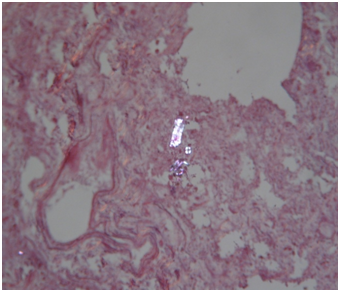

Histology: Acute emphysema was the prominent observation; edema and hemorrhages were also present.4 In 9 cases (Figures 3-6), exogenous material in the airways, comprehensive of planktonic boli in the lower branches, clearly demonstrable at polarization microscope (and possibly confirmable at SEM’s elemental analysis with EXD). Zoo- and phytoplankton have been better identified in the UV microscope. It is mandatory to differentiate the planktonic material from gastric content, regurgitated and aspirated (Figure 7 & 8).

Figure 7 Same case of Fig. 7. Fragments of food (cooked meat and tuber cells) in the main stem bronchus (EE, 240X).

Figure 8 Same case of Fig. 7. Plant material identified in the esophageal mucosal laceration (EE, 480X, UV).